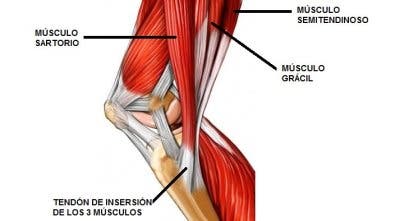

La pata de ganso se encuentra en la parte lateral interna de la rodilla, debajo de la línea articular, y tiene una amplia zona de inserción tendinosa en la meseta tibial interna y una bolsa sinovial que amortigua golpes y roces. La pata de ganso está formada por los tendones de tres músculos, como observamos en la siguiente imagen:

Como podemos observar, los músculos son:

- Sartorio.

- Grácil, también llamado recto interno.

- Semitendinoso.

- La pata de ganso está formada por 3 músculos (sartorio, grácil y semitendinoso).